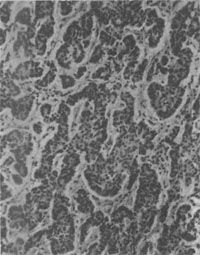

镜下见细胞较小,形态一致,为圆形或多角形,核小而规则。胞浆轻度嗜碱性,有嗜银颗粒,颗粒内含5-羟色胺。细胞形成实体状或索状胞巢,有时可见其中有假菊形团样结构(图10-28)。电镜观察可见细胞浆内有直径100~300nm的球形分泌颗粒,颗粒中有有一电子致密核心,颗粒周边有高电子密度的界膜。常限于粘膜及粘膜下层,少数可达浆膜层。发生在阑尾的类一般恶性度较低,转移率为3%。但发生在其他肠段及其他部位的类,则有约2/3为恶性者,并常转移到肝。

结肠类<a href=癌"/>

图10-28 结肠类